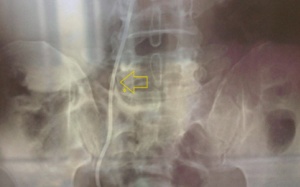

Sau khi phẫu thuật mổ sỏi thận, không thấy đau nữa, cụ ông 75 tuổi không tái khám và lấy ống thông theo hẹn của bác sỹ cho tới khi thấy đau tức vùng bụng.